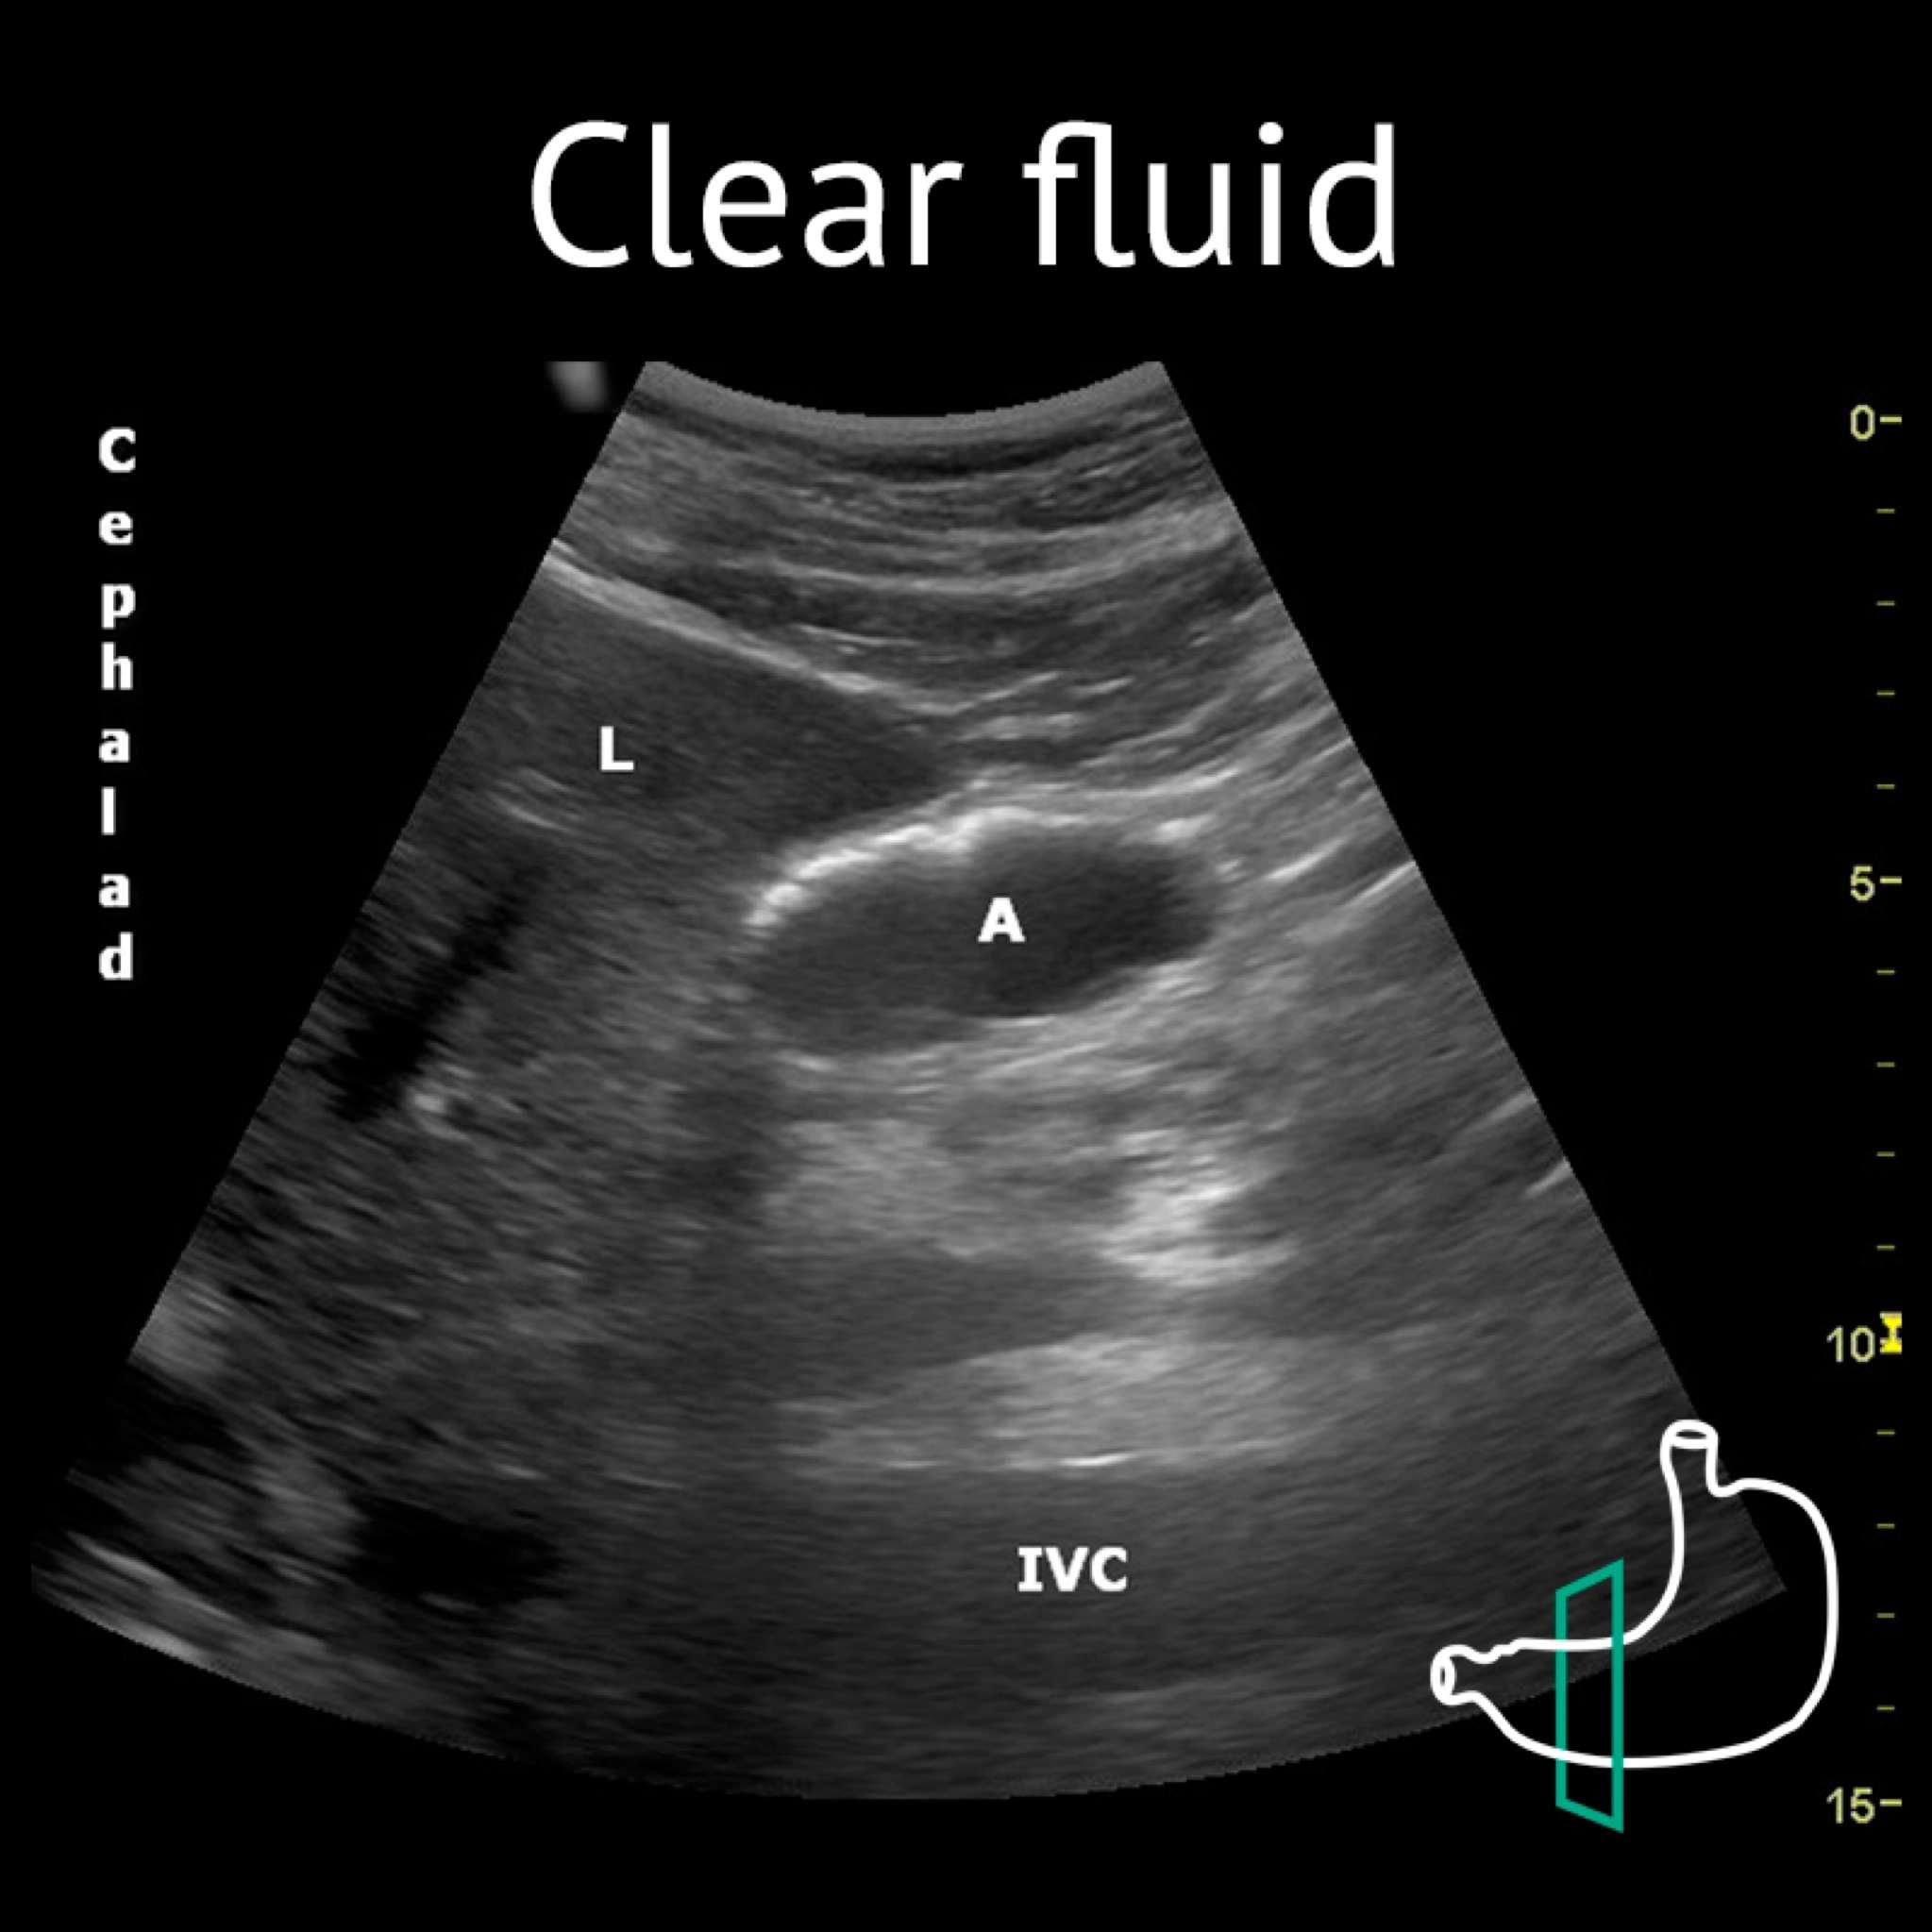

A: antrum; L: liver; IVC: inferior vena cava